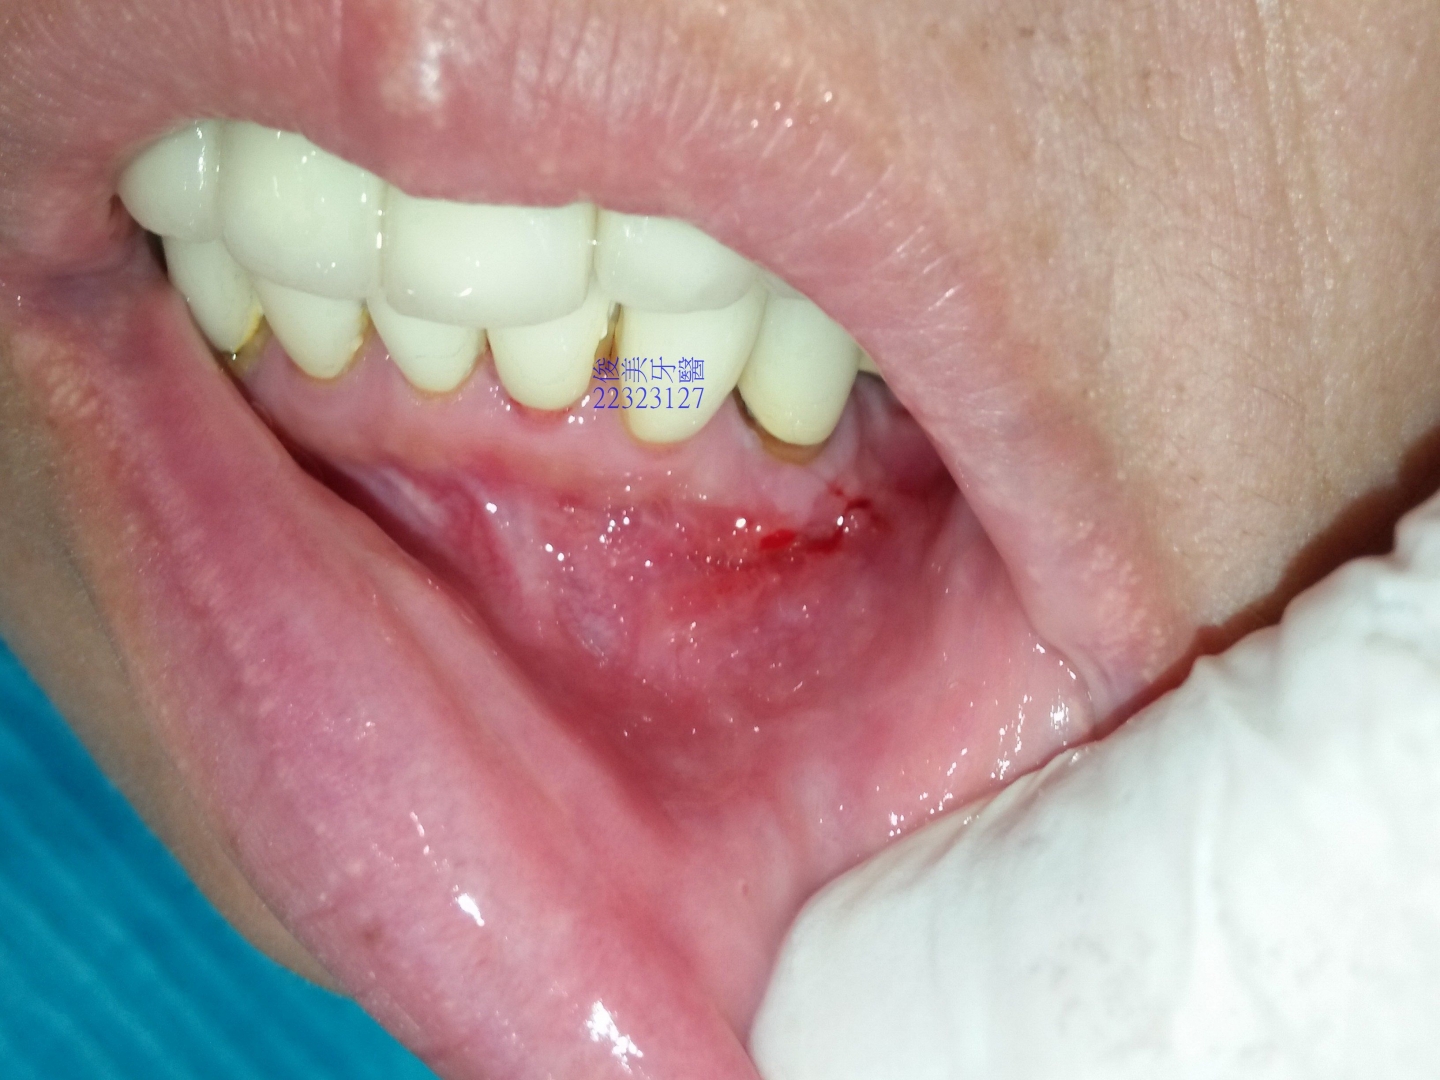

患者多年前抽過神經的牙齒,有病灶,牙根尖底部有病變,檢查時皆有提醒患者注意,直到近期,口腔內出現小腫苞,

一翻開牙齦就發現不正常組織已穿透骨頭。

牙根已裸露無骨頭保護。